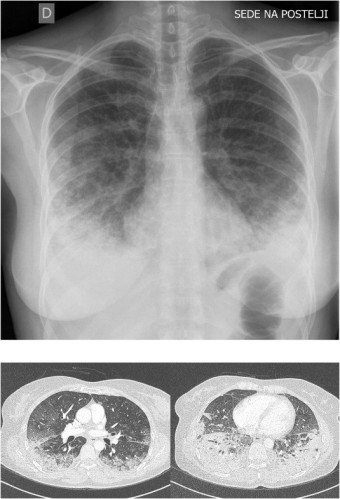

급성 폐렴의 원인

급성 폐렴은 다양한 병원체에 의해 발생하며, 주요 원인은 다음과 같습니다.

세균 감염 : 폐렴구균, 황색포도상구균, 헤모필루스 인플루엔자 등 여러 세균이 폐렴의 원인이 될 수 있습니다. 특히 폐렴구균은 세균성 폐렴의 가장 흔한 원인으로 알려져 있습니다.

바이러스 감염 : 인플루엔자 바이러스, 코로나바이러스, 호흡기 세포융합 바이러스(RSV) 등이 폐렴을 유발할 수 있습니다. 바이러스성 폐렴은 특히 어린이와 노인에서 흔하게 발생합니다.

곰팡이 감염 : 면역력이 저하된 환자에서 아스페르길루스나 히스토플라스마와 같은 곰팡이가 폐렴을 일으킬 수 있습니다.

기타 원인 : 흡인성 폐렴은 음식물이나 구토물이 기도로 들어가 폐에 염증을 일으키는 경우로, 의식 저하나 연하 곤란이 있는 환자에서 발생할 수 있습니다.